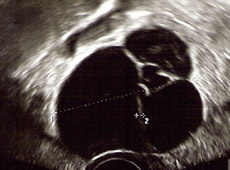

Zyste gebärmutter entfernen ambulant. Das arthroskopische Entfernen der Baker-Zyste findet meist ambulant statt. Bei einer Bauchspiegelung Laparoskopie werden unter Vollnarkose drei sehr kleine Schnitte in die Bauchdecke gesetzt. Durch diese Schnitte werden Kamera und Spezialinstrumente in den Bauchraum eingeführt.

Laparoskopisch gestützte Gebärmutterentfernung Die Entfernung von einfachen Eierstock Zyste n stellt in der Regel auch beim ambulanten Operieren kein Problem dar. Jetzt soll ich sie operativ entfernen lassen. Besteht ein Zweifel über die Gutartigkeit der Zyste sollte die Zyste zur Sicherheit immer entfernt werden.

Der Arzt wird dann zu einer operativen Bauchspiegelung raten wenn gutartige Geschwüre wie Gebärmutterknoten Myome oder Zysten an den Eierstöcken Beschwerden bereiten und klein genug sind um mittels Bauchspiegelung entfernt zu werden.

Moderne Operationstechniken und umfassende Nachsorge helfen den Patientinnen nach dem Eingriff ihr Leben wieder aktiv anzugehen. Jetzt soll ich sie operativ entfernen lassen. Ebenfalls werden bei der Entscheidung eventuell vorher bekannte Wundheilungsstörungen und andere Vorerkrankungen beachtet. Bei einer Bauchspiegelung Laparoskopie werden unter Vollnarkose drei sehr kleine Schnitte in die Bauchdecke gesetzt. Zuerst hiess es nur engmaschig überwachen dann habe ich 3 Monate lang Hormone bekommen. Ist eine Patientin häufig von symptomatischen Zysten geplagt kommt die Entfernung der gesamten Gebärmutter Hysterektomie in Betracht. Sie kann in einem ambulanten Operationszentrum oder einem Krankenhaus erfolgen.